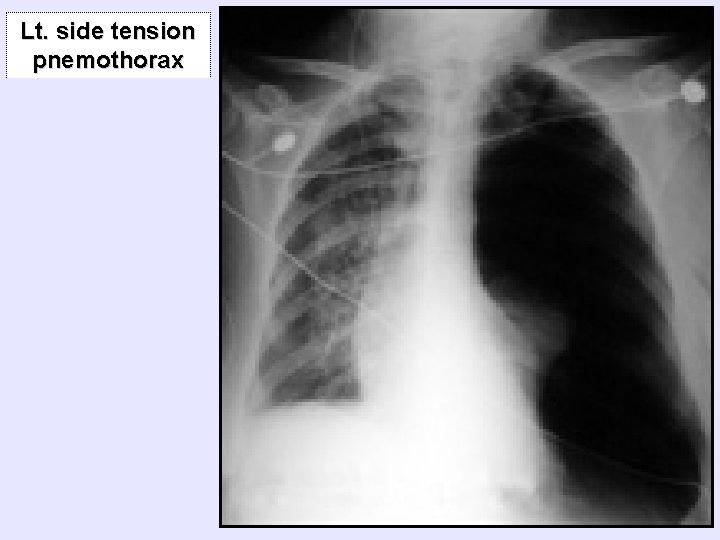

Lt. side tension pnemothorax